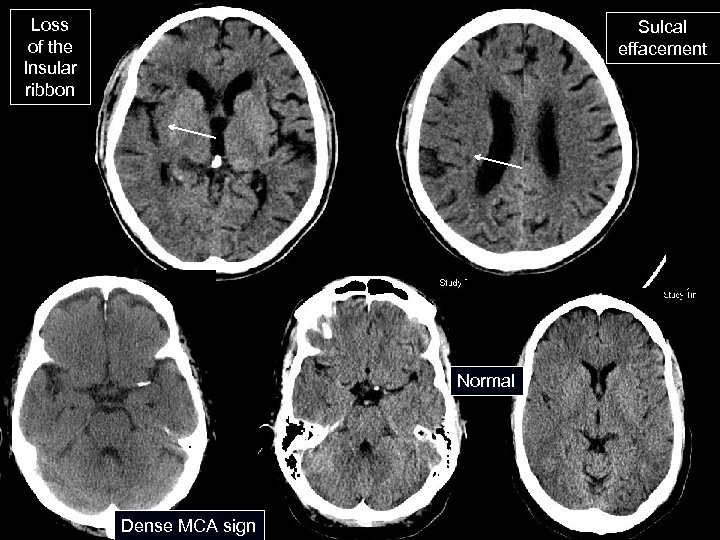

CT Head Without Contrast n Initial test of choice for all acute strokes High sensitivity for ICH n Early infarct signs: dense MCA sign, loss of the insular ribbon, sulcal effacement n Obvious evidence of infarction should lead to rethinking the time of onset. Usually CT not obvious until 24 hours n Poor sensitivity even several days after onset for brainstem or small infarcts n

Loss of the Insular ribbon Sulcal effacement Normal Dense MCA sign